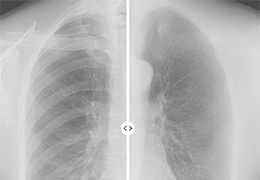

提供相配视图选项,以减少所需的曝光次数,并提供更清晰的感兴趣区域视图。